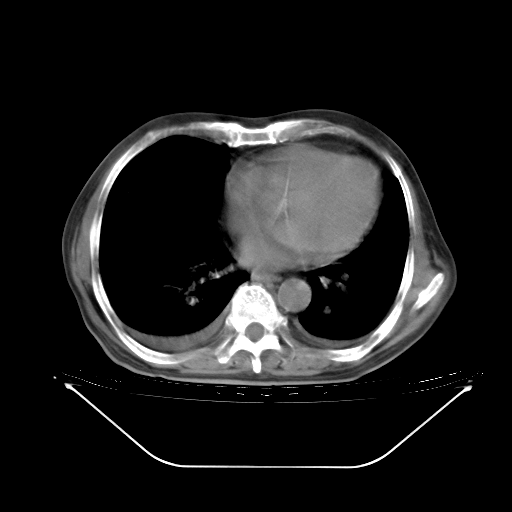

今天复查肺部CT,发现双肺广泛磨玻璃样改变。所以我把3月19日和5月9日相隔50天的肺部CT上传。请大家会诊。

2009年3月19日肺部CT片。

5月9日肺部CT(在4月27日齐鲁医院肺部CT描述部分肺组织磨玻璃样改变,12天后肺组织广泛磨玻璃样改变)